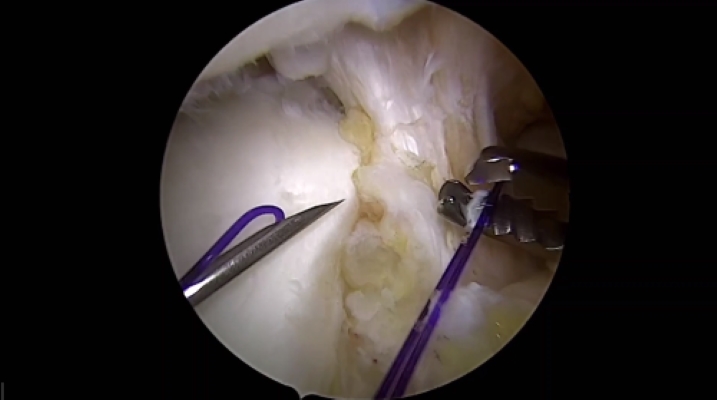

Erkenntnisse zur Wirkung der Produktdosis bei Autologer Chondrozytentransplantation bei Knorpeldefekten im Kniegelenk – Überblick der CO.DIS-Studie

Knorpelzelltranplantation an der Patella vs. Femur - Klinische Ergebnisse und Erfolgsraten im Vergleich

Vorteile der Autologen Chondrozytentransplantion mit Spheroid-Technologie vs. Mikrofrakturierung – Ergebnisse einer Nicht-Unterlegenheitsstudie nach 36 Monaten (CO.WISI)

Sicherheit und Wirksamkeit der Autologen Chondrozytentransplantation bei Jugendlichen im Vergleich zu jungen Erwachsenen (PIP-Studie)

Wichtigste Studienergebnisse aus dem Zulassungsprozess des Produktes Spherox für die zentrale europäische Zulassung – Überblick und Diskussion